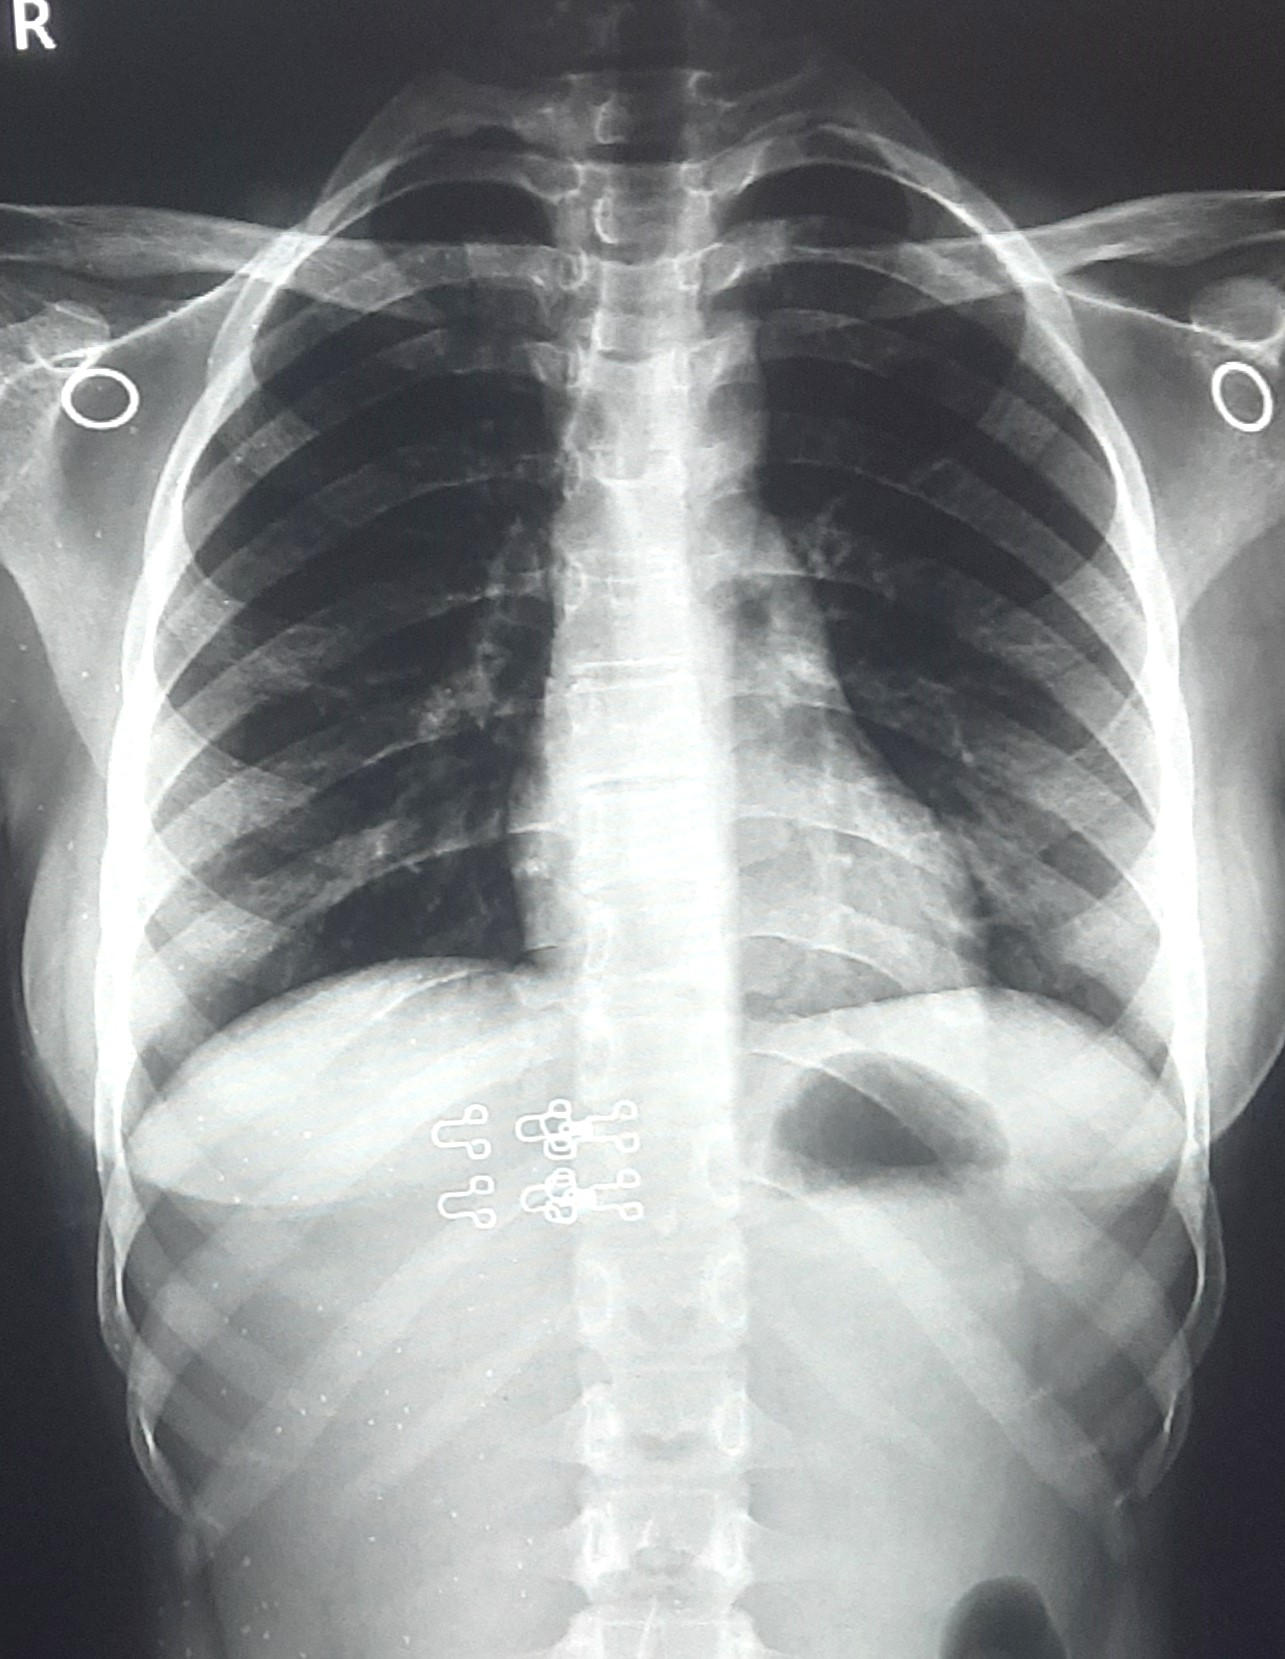

| 338 | IGGMC, Nagpur, Nagpur | P2 | 29-4134 | Rupesh Dongse | Consent taken on Paper | 43 Yrs. |

Provisional Diag : Consolidation

Final Diag : Bilateral Consolidation Community Acquired Pneumonia With Type 1 Respi Failure In Cronic Alcoholic |

Non-TB Case (Confirmed) | Bilateral Consolidation | Abnormality visible on x-ray |